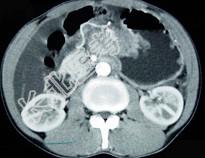

- 单项选择题男,65岁, 中上腹痛腹胀、消瘦、乏力、纳差,影像检查如图, 最可能的诊断是  (    )

- A、胃间质瘤

- B、萎缩性胃炎

- C、肥厚性胃炎

- D、胃窦癌

- E、胃淋巴瘤